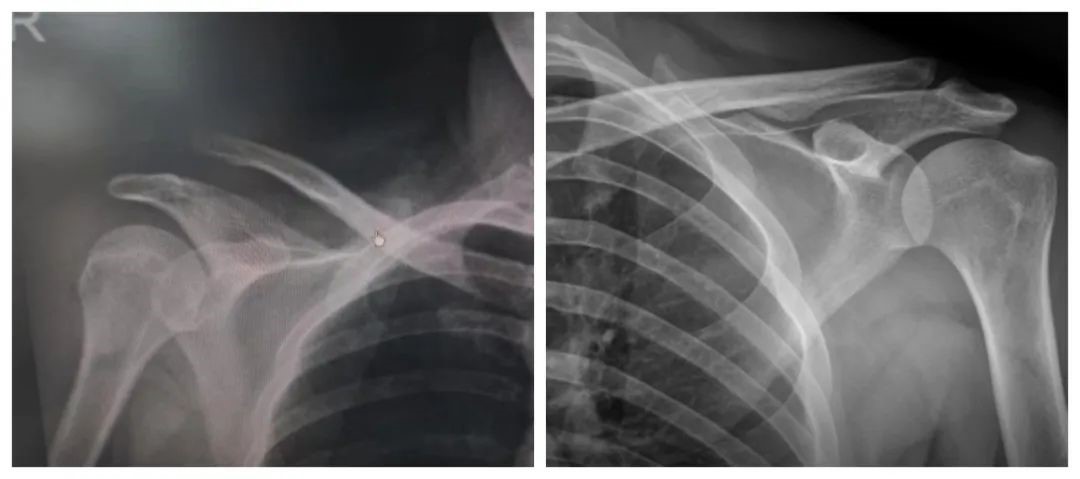

肩锁关节脱位 正常肩锁关节

肩锁关节是上肢运动的支点,在肩胛带功能和动力学上占有重要位置,是上肢外展、上举不可缺少的关节之一,同时参与肩关节的前屈和后伸运动。当肩锁关节发生损伤而脱位时,可以看出局部高起,双侧对比较明显,可有局部疼痛、肿胀及压痛;伤肢外展或上举等活动比较困难,前屈和后伸运动亦受限,局部疼痛加剧,检查时肩锁关节处可摸到一个凹陷,可摸到肩锁关节松动。